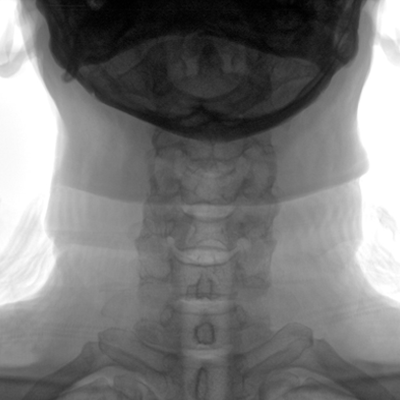

大尺寸動態(tài)平板探測器,高DQE、低噪聲、圖像清晰。采用多分辨率圖像增強處理技術(shù),不同部位不同圖像處理算法,滿足客戶多樣化的需求。

采用智能變頻脈沖透視技術(shù),優(yōu)化圖像質(zhì)量的同時降低輻射劑量,呵護醫(yī)患健康